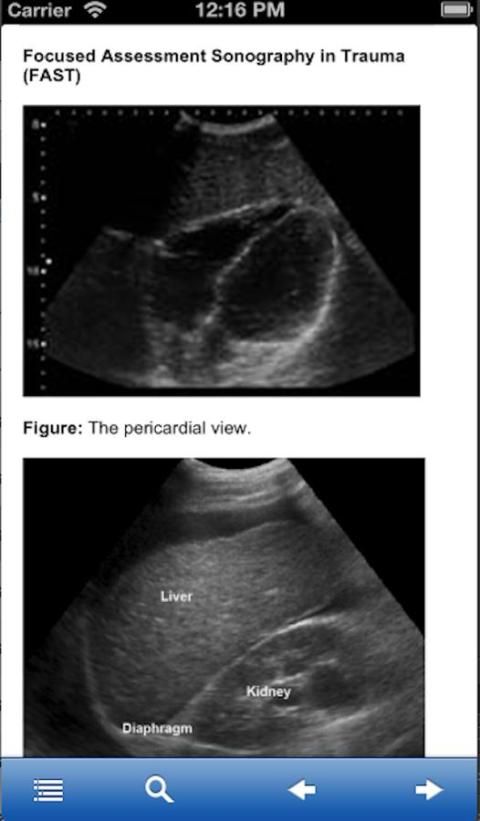

Fokus Penilaian Sonografi Trauma